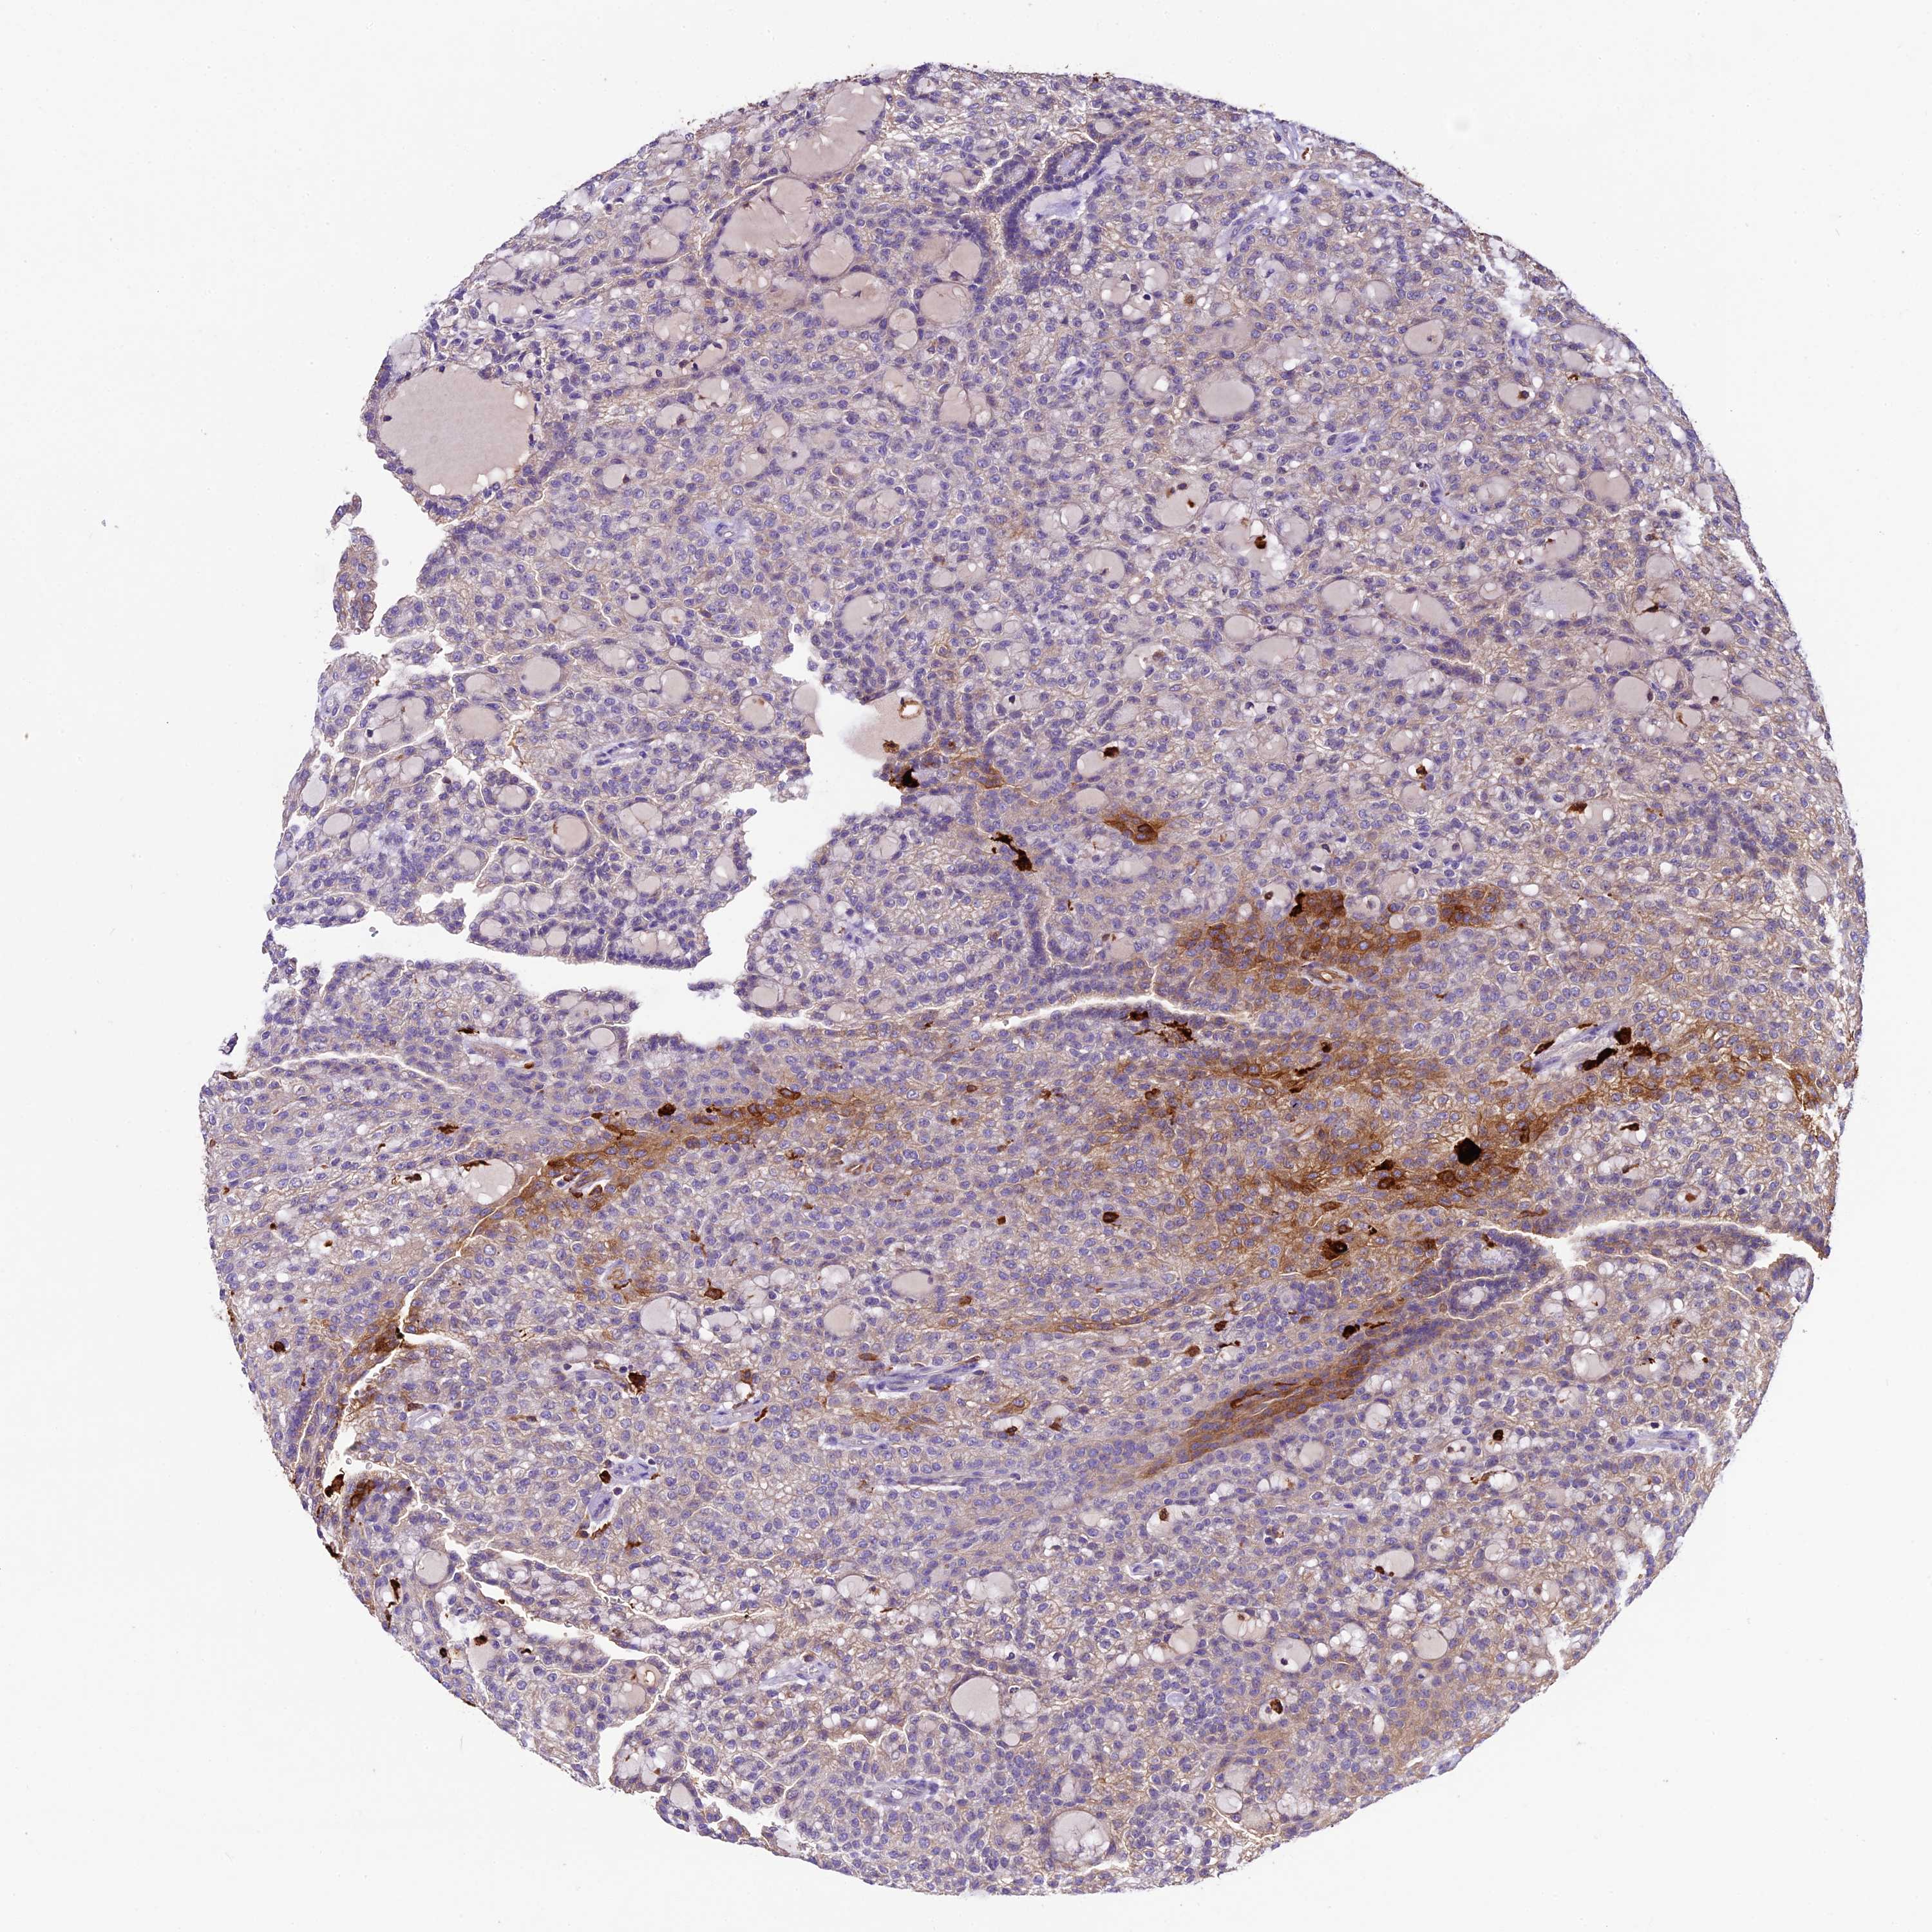

KIDNEY RENAL PAPILLARY CELL CARCINOMA (TCGA) - Interactive survival scatter ploti

The Survival Scatter plot shows the clinical status (i.e. dead or alive) for all individuals in the patient cohort, based on the same data that underlies the corresponding Kaplan-Meier plots. Patients that are alive at last time for follow-up are shown in blue and patients who have died during the study are shown in red.

The x-axis shows the expression levels (FPKM) of the investigated gene in the tumor tissue at the time of diagnosis. The y-axis shows the follow-up time after diagnosis (years). Both axes are complimented with kernel density curves demonstrating the data density over the axes. The top density plot shows the expression levels (FPKM) distribution among dead (red) and alive patients (blue). The right density plot shows the data density of the survived years of dead patients with high and low expression levels respectively, stratified using the cutoff indicated by the vertical dashed line through the Survival Scatter plot. This cutoff is automatically defined based on the FPKM cutoff that minimizes the p-score. The cutoff can be changed by dragging the vertical line or by entering a cutoff value in the square labeled "Current cut-off".

Under the Survival Scatter plot the p-score landscape (black curve; left axis) is shown together with dead median separation (red curve; right axis). Dead median separation is the difference in median mRNA expression between patients who have died with high and low expression, respectively. It is calculated as follows: median FPKM expression of dead patients with high expression - median FPKM expression of dead patients with low expression. This is intended to aid the user in visually exploring custom cutoffs and the associated p-scores and dead median separation.

Individual patient data is displayed and can be filtered by clicking on one or more of the category buttons on the top of the page. Categories describing expression level and patient information include: high, low, alive, dead, female, male and tumor stages. The scale of the x-axis can be toggled between linear and log-scale by clicking on the "x log" button. Mouse-over function shows TCGA ID, patient information and mRNA expression (FPKM) for each patient.

& Survival analysisi

Kaplan-Meier plots summarize results from analysis of correlation between mRNA expression level and patient survival. Patients were divided based on level of expression into one of the two groups "low" (under cut off) or "high" (over cut off). X-axis shows time for survival (years) and y-axis shows the probability of survival, where 1.0 corresponds to 100 percent.

CILP2 is not prognostic in Kidney Renal Papillary Cell Carcinoma (TCGA)